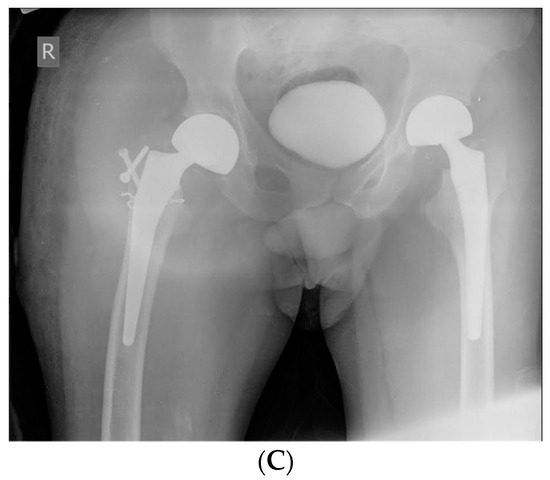

Case 1. Femoral neck fractures are common in the elderly population, who are frequently confronted with osteoporosis. Though rare, these fractures can also occur, mainly unilaterally, in younger individuals following a high-energy trauma. Only a few articles describe bilateral simultaneous femoral neck fractures as an injury resulting from seizures, and these were not assessed in PwH. We report a case of a bilateral femoral neck fracture in a 50-year-old male with severe haemophilia B (SHB) following a generalized convulsion. The patient was addressed to the emergency department for a generalized tonic-clonic seizure episode, and the patient was known and had been treated for epilepsy; he presented with evidence of SHB and multiple haemophilic arthropathies without a history of trauma or any comorbidities. On examination, the lower limbs were externally rotated; there were no distal neurovascular deficits, open wounds, or trauma evidence. Radiography revealed a bilateral femoral neck fracture (Figure 1A,B). Under rigorous hemostatic control, the orthopaedic surgeon team decided to intervene in one stage, and bilateral simultaneous hip arthroplasty was performed. The right hip joint was complicated with pertrochanteric fracture and needed additional osteosynthesis with screws (Figure 1C). Postoperatively, bedside hip range of motion exercises were started within days 2–3 after surgery, continuing with an enhanced rehabilitation program. The patient had a favourable outcome without any post-operative complications and was discharged after 30 days. Overall costs were EUR 86,856.05, and the factor concentrate accounted for 91.75% of expenditures (recombinant FIX, ~EUR 79,697.48). However, these two simultaneous major interventions had a decisive, favourable effect on the costs and rehabilitation of the patient. Due to a forceful contraction of muscles during an episode of generalised tonic-clonic seizures, a fracture or dislocation may develop.

Figure 1.

(A) Case 1—X-ray: Right femoral neck fracture—before surgery. (B) Case 1—X-ray: Left femoral neck fracture—before surgery. (C) Case 1—X-ray: Bilateral simultaneous hip arthroplasty, the right hip joint was complicated with pertrochanteric fracture and needed additional osteosynthesis with screws.